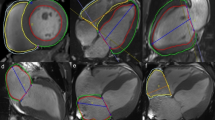

LA volume was analyzed following the area and length method13 using 2- and 4-chamber long axis cine images with commercial software (Circle Cardiovascular Imaging Inc, Calgary, Canada) and indexed to BSA. LA maximum volume (LAVmax) was assessed at LV end systole and LA minimum volume (LAVmin) at LV end diastole. Phasic LA strain was analyzed using feature tracking software (TomTec, Germany). LA endocardial contours were first drawn manually and propagated through cardiac phases along the 2-, 3-, and 4- chamber views. Manual adjustment was made when needed. Peak LA strains were assessed as the average peak strain values of the 3 longitudinal planes (Fig. 1). LV longitudinal strain was analyzed by feature tracking (Circle Cardiovascular Imaging Inc, Calgary, Canada) in order to capture the strain of full myocardial thickness. The epi- and endocardial contours were drawn manually on the end diastolic phase of the 2-, 3-, and 4-chamber cine images and propagated by the software to calculate 2D peak systolic longitudinal strain. All image analysis was performed by experienced operators.

The left panel represents the respective 2-, 3-, 4-, chamber cine views from a normal control subject with the green feature tracking contours overlaying the left atrial wall. The right panels are the corresponding left atrial strain graphs obtained from each view as well as representative strain graphs from subjects with diastolic dysfunction grades 1, 2, and 3.

Our study subjects (n = 164) consisted of four groups: normal controls (n = 32), grade I DD (n = 69), grade II DD (n = 42), and grade III DD (n = 21). On average, patients with DD were 60 ± 14 years old and about half (N = 63) had advanced DD (grades II or III). Normal LVEF (> 50%) was present in 18 (14%) patients. Baseline characteristics of each DD grade are displayed in Table 1. Examples of phasic LA strains are shown in Fig. 1 where graded decreases of LA strains are shown from normal to grade 1, II and III diastolic dysfunction. Phasic LA strains and LAEF were progressively lower with increasing severity of DD (p < 0.001) (Fig. 2A–C, F; Table 2). Similarly, LV longitudinal strain was also progressively lower (Fig. 2G). Conversely, LAVmin and LAVmax were significantly higher with increasing severity of DD (p < 0.001) (Fig. 2D, E).